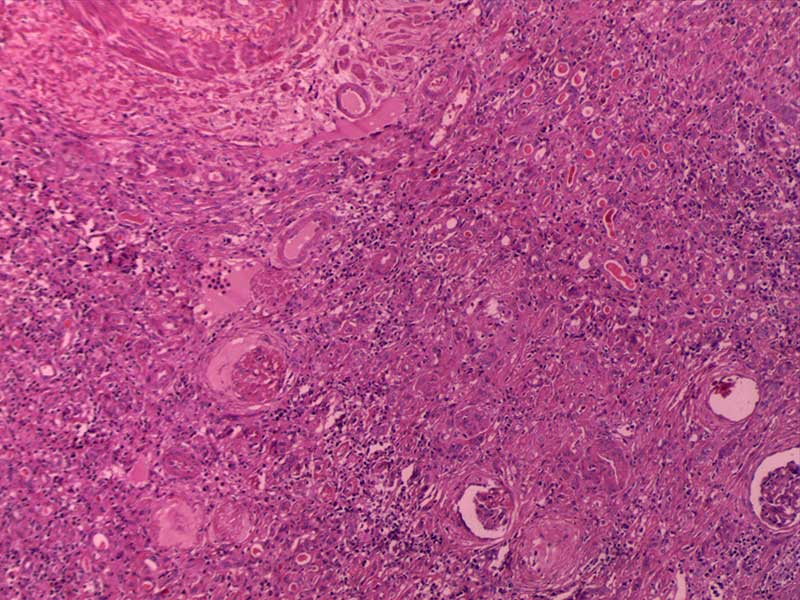

肾透明细胞癌-10倍

纤维肉瘤10-倍